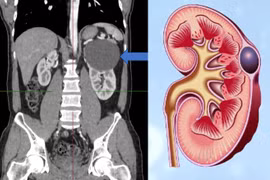

Đau tức hố thắt lưng phải nhiều ngày, không sốt trẻ đã phải phẫu thuật vì dị tật bẩm sinh niệu quản. Nếu không phẫu thuật kịp thời trẻ sẽ mất chức năng thận.